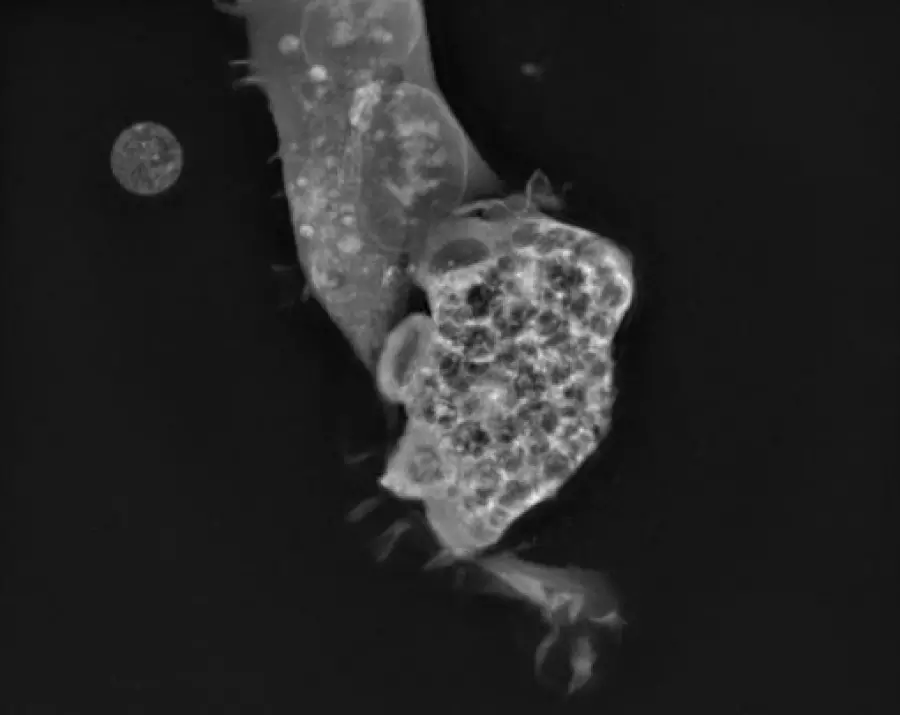

Naegleria fowleri atakuje lidskou buňku. Autor: Ronald Malych

První nemocí, proti které se podařilo najít potenciálně průlomovou terapii, je PAM. Způsobuje ji smrtící mikrobiální patogen Naegleria fowleri. Lidé se touto teplovodní „mozkožravou" amébou infikují většinou při plavání nebo jiných rekreačních aktivitách ve vodě.

Skrze nosní sliznici a čichový nerv může améba napadnout lidský mozek. Ačkoli toto onemocnění není příliš časté (v USA bylo doteď zaznamenáno méně než 200 případů), je i přes veškerou moderní lékařskou péči z 97 % smrtelné. Příznaky začínají obvykle pět dní po expozici a pacienti po několika dnech podlehnou poškození mozku.